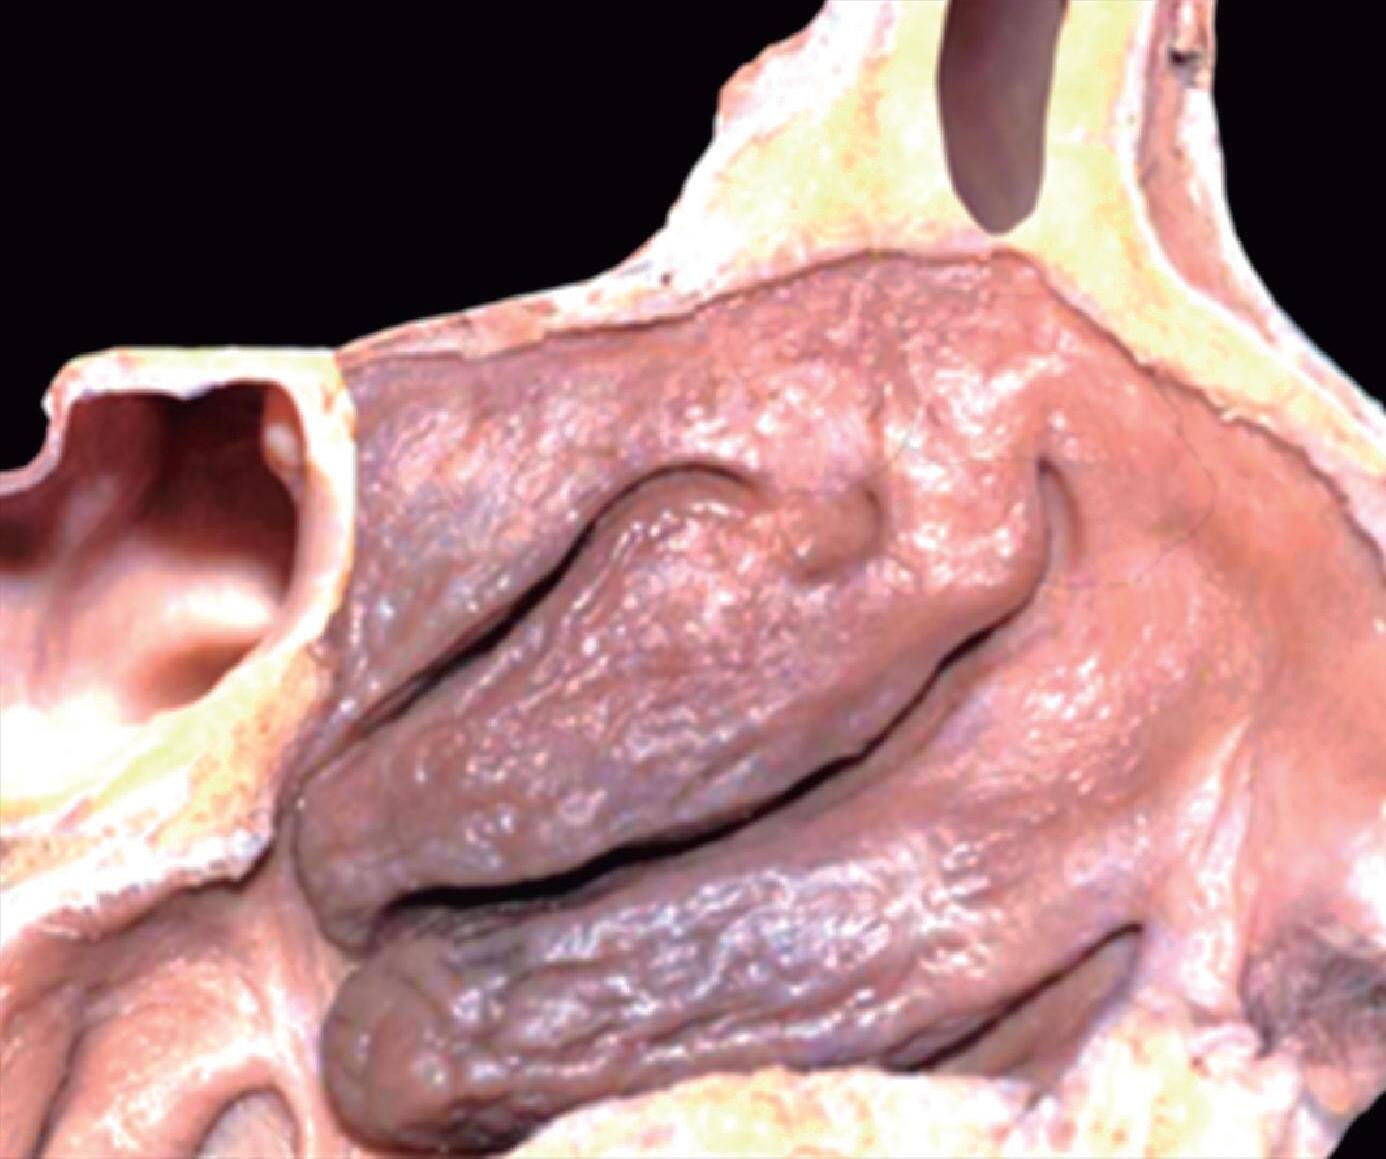

1-13. Montagem em aspecto endoscópico e peça anatômica (Bagatella) demonstrando a relação do processo uncinado e bulha etmoidal com a parede medial da órbita: (1) porção meatal da concha média; (2) processo uncinado; (3) bulha etmoidal; (4) parede medial da órbita.